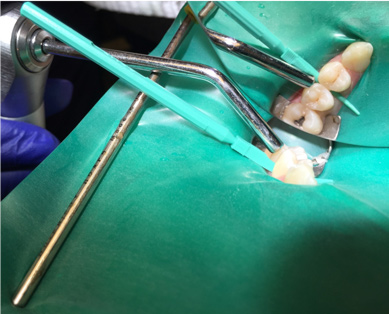

Fig 4. A wedge is used if more separation is required.

Figure 4

4. Remove the separator. If needed to accommodate the applicator, utilize one of the wedges provided in the proximal resin infiltration kit to create more space between the teeth (Figure 4).